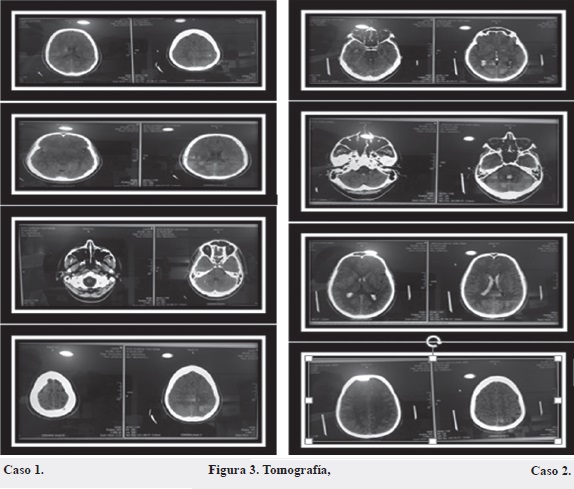

Paciente masculino de 27 años, remitido del Hospital de Sarare (Arauquita, Arauca) por fístula dural posterior derecha más ataque cerebrovascular (ACV) hemorrágico. El paciente ingresa al Hospital Universitario Los Comuneros, de Bucaramanga, el 19 de diciembre de 2014 presentando cuadro clínico con dos semanas de evolución de cefalea y parestesia en hemicara derecha y miembro superior derecho, que aumentó en las cuarenta y ocho horas previas a la consulta. En la consulta inicial realizada en el Hospital de Sarare fue valorado por el servicio de medicina interna, el cual solicitó TAC cerebral simple, con hallazgo de hiperdensidad a nivel clinoideo derecho y frontal posterior por posible malformación, requiriendo ayuda diagnóstica con Angio-TAC; reporte de pequeño nicho malformativo a nivel frontal posterior derecho por la presencia de fístula dural y vasoespasmo severo en M1; fue remitido para manejo por radiología intervencionista. Se diagnosticó hemorragia intracerebral en hemisferio no específico (Figura 3). Tras valoración por neurología se diagnostica enfermedad de moyamoya no quirúrgica, el paciente requiere seguimiento estrecho por parte de neurología. Manejo con nimodipino 30 mg / cada doce horas.

El paciente ingresa al servicio de urgencias del Hospital Universitario Los Comuneros el 5 de enero de 2015, en regulares condiciones generales, con rigidez de nuca, somnolencia, desorientación. La tomografía cerebral extrainstitucional evidencia ocupación por material hiperdenso hemático de sistema ventricular a nivel de los ventrículos laterales, III y IV ventrículo, ocupación por material hiperdenso hemático en los cuernos temporales de ventrículos laterales, valorado por neurocirugía. Se inicia vigilancia neurológica estricta, sin soporte vasoactivo ni ventilatorio y se solicitan paraclínicos de ingreso. Se diagnostica hemorragia intraventricular de etiología de estudio (Figura 3). Manejo médico, vigilancia neurológica estricta. Los resultados de la panangiografía solicitada muestra patrón de moyamoya bilateral compatible con enfermedad de moyamoya tipo 1.

La enfermedad de moyamoya se diagnostica siguiendo los criterios establecidos por el Comité de Obstrucción Espontánea del Círculo de Willis, del Ministerio de Salud japonés (Tabla 3). Dichos criterios se apoyan en el análisis de estudios de neuroimagen como angiografía, angiorresonancia, tomografía computada por emisión de fotón único (SPECT), tomografía por emisión de positrones (PET), resonancia magnética de perfusión, dúplex y doppler transcra¬neal (DTC) (12). Para los estudios de caso presentados, el diagnóstico se realizó con análisis de TAC cerebral simple y Angio-TAC para el caso 1, y de tomografía cerebral para el caso 2 (Figura 3).

En el presente trabajo se reportaron dos casos de pacientes tratados en el Hospital Universitario Los Comuneros de Bucaramanga (Santander) con el diagnóstico de moyamoya, entre diciembre de 2014 y enero de 2015. En ambos casos los pacientes consultaron por una fuerte cefalea. El paciente del caso 1, hombre de 27 años de edad, sin antecedentes de importancia, con clínica de dos semanas de cefalea y parestesias en hemicara derecha y miembro superior derecho, presentó hemorragia intracerebral en hemisferio no específico y tras análisis de estudios radiológicos se halló hiperdensidad a nivel clinoideo derecho y frontal posterior por malformación a nivel frontal posterior derecho más fístula dural y vasoespasmo severo de M1. Para su tratamiento se indica manejo médico, iniciando con reanimación hídrica y manejo del vasoespasmo con calcioantagonistas (nimodipino) 30 mg / cada doce horas y estudios de extensión. La valoración por neurología determinó paciente con enfermedad de moyamoya no quirúrgica, el cual requiere seguimiento estrecho por parte de neurología, diagnóstico realizado con el apoyo de resultados de TAC cerebral simple y panangiografía cerebral. En el resultado del TAC cerebral simple se observa hiperdensidad a nivel clinoideo derecho y frontal posterior por posible malformación, la panangiografía cerebral reporta pequeño nicho malformativo a nivel frontal posterior derecho por la presencia de fístula dural y vasoespasmo severo en M1.

En el caso 2, el paciente masculino de 46 años de edad, sin antecedentes aparentes, consultó por cuadro de quince días de evolución de cefalea que se asocia a pérdida de conciencia con posterior desorientación y lenguaje incoherente. Tras estudio topográfico cerebral extrainstitucional se evidencia ocupación por material hiperdenso hemático de sistema ventricular a nivel de los ventrículos laterales, III y IV ventrículo, ocupación por material hiperdenso hemático en los cuernos temporalis de ventrículos laterales, valorado por neurocirugía; debido a no disponibilidad de angiotomografía ni panangiografía institucional, solicitan RMN cerebral más angiorresonancia. Se diagnostica hemorragia intraventricular de etiología a estudio. Posterior a estos estudios, neurocirugía determina ordenar panangiografía cerebral con conclusión de patrón de moyamoya bilateral compatible con enfermedad de moyamoya tipo I.